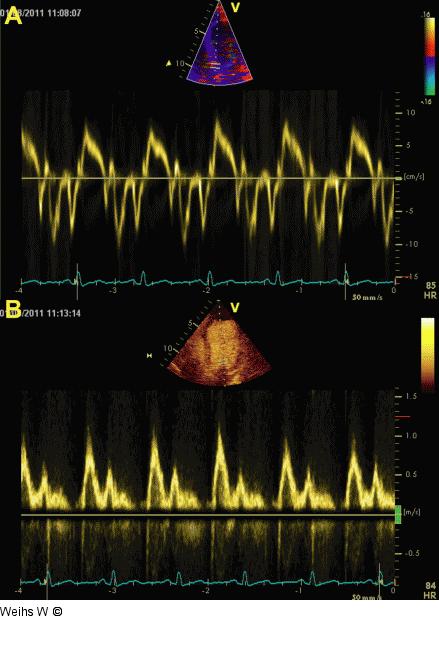

Abbildung 3a-b: TDI Die Geschwindigkeiten des Tissue-Dopplers (TDI), abgeleitet vom septalen Mitralanulus (a) und der transmitrale Fluss (b) ergeben keinen Hinweis auf erhöhte linksventrikuläre Füllungsdrücke. |

Die Geschwindigkeiten des Tissue-Dopplers (TDI), abgeleitet vom septalen Mitralanulus (a) und der transmitrale Fluss (b) ergeben keinen Hinweis auf erhöhte linksventrikuläre Füllungsdrücke. |